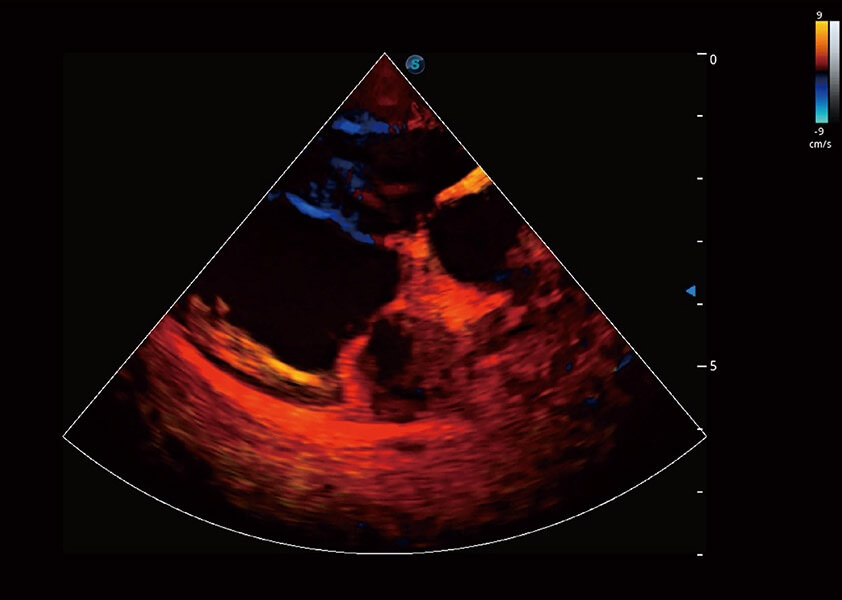

ProPet 60 作為一款高端臺(tái)式動(dòng)物超聲設(shè)備,為動(dòng)物醫(yī)生的日常診斷提供了一系列貼合動(dòng)物臨床需求、解決臨床實(shí)際問題的高級成像功能。憑借全系列高清探頭,滿足醫(yī)生對腹部、心臟、生殖、淺表、肌骨等成像的所有需求,切實(shí)幫助您提升檢查效率,提高診斷信心。

獸用彩色多普勒超聲診斷系統(tǒng)